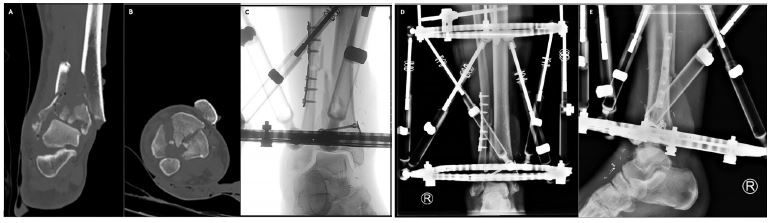

Hybrid fixator systems consist of at least three tensioned wires, which are placed in the distal fragments of the fracture site and connected through a circular frame (Figure 2). Mostly, hybrid external fixation systems can be used in the ankle ligamentotaxy technique, where it is possible to support the entire weight load [4].

Figure 2: Primary hybrid external fixation in combination with plate osteosynthesis and lag screws in an open tibial pilon IIA fracture. We present the case of a 55-year-old man with an open fracture IIA of the tibial pylon AO type 43-C3, who came through the trauma room. After preoperative CT scans in the emergency [(A) coronal plane, (B) axial plane] temporary fixation and soft tissue conditioning were performed. The extensive soft tissue defect on the anteromedial side was covered with a microvascular radial artery free flap. Subsequently, the length and rotation of the fibula conminuto were restored and the articular surface of the tibial pylon was reconstructed using minimally invasive plates and lag screws, (C) intraoperative fluoroscopy]. Finally, we stabilized the tibial pilon fracture using a hybrid circular frame with Kichner wires tensioned in the distal fragments and Schanz screws in the proximal tibia, [(D) Postoperative AP radiograph, (E) Postoperative lateral radiograph.

Source: Mair O, Pflüger P, Hoffeld K, Braun K, Kirchhoff Ch, Biberthaler P, Crönlein M. Management of Pilon Fractures—Current Concepts. Front. Surg. 2021; 8:764232. doi: 10.3389/fsurg.2021.764232.